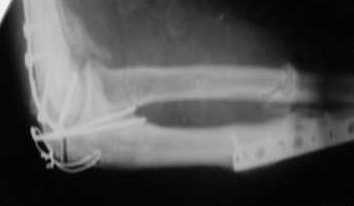

Подскажите пожалуйста, как можно в дальнейшем этому больному помочь. В марте первая

операция, пришлось оперировать на 16 сутки в виду инфицированных садин и анемии. Заживление

первичным натяжением, ранняя разработка после операции, а через 2 нед болевой синдром,и

постепенно движения в локтевом суставе ограничились до полного анкилоза. Повторно через 4

месяца вторая операция - артролиз, удаление оссификатов, удаление фиксаторов,

реостеосинтез этой же реконструкционной пластиной и винтом. Интраоперационно после

удаления оссификатов и фиксаторов обнаружил, что переломы не сросшиеся, поэтому пришлось

синтезировать заново. Зажила рана первично, объем движений в локтевом суставе сгибание 70,

разгибание160, ротационные движения востановились полностью, вроде бы успокоились.

Опять постепенно в течении 8 нед после повторной операции постепенно движения ограничились

до 80 - 110, на снимке оссификат. Снимки во вложении, буду рад Вашим советам. Спасибо!